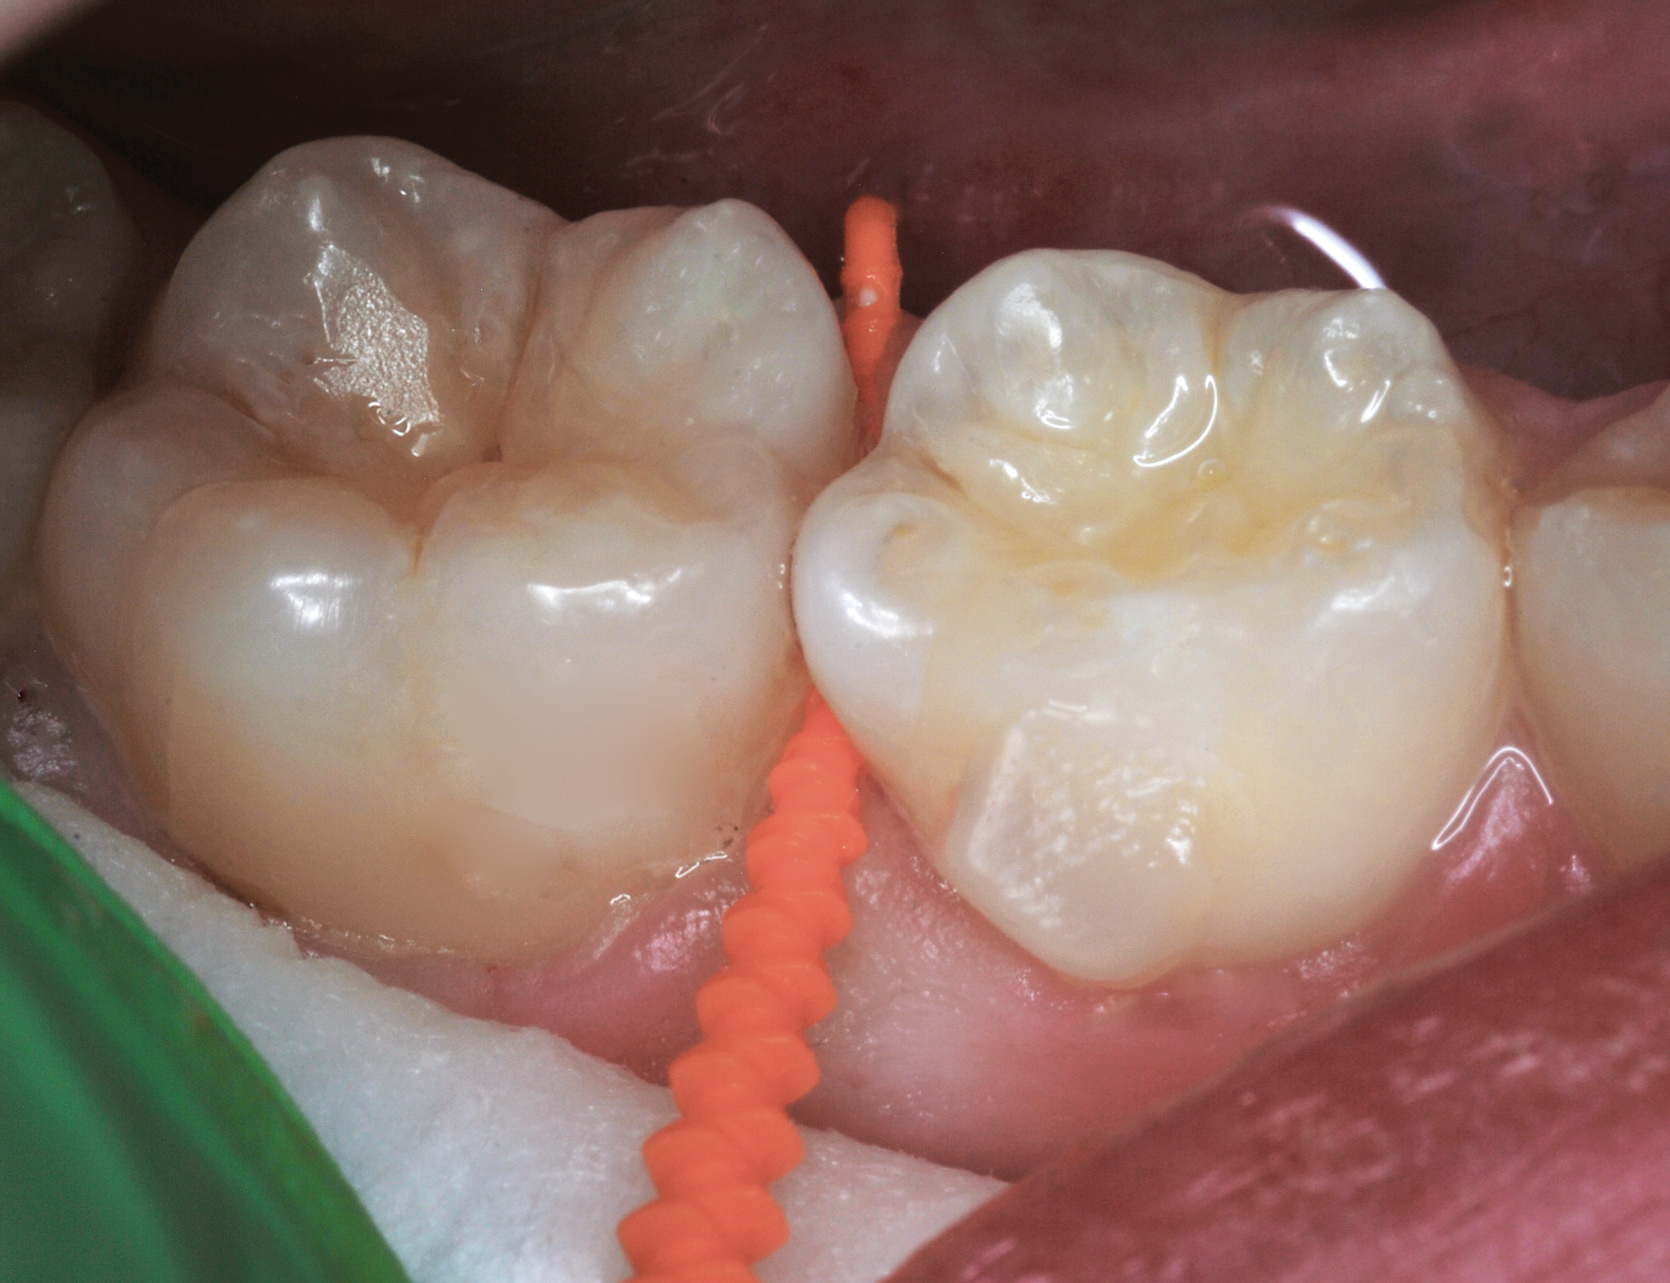

Fig 8. Caries prevention with SDF is critical on distal surfaces of primary second molars to avoid caries infection on mesial surfaces of permanent first molars. Note the Class 2 restorations in both primary molars in this 9-year-old patient whose first molar needed occlusal resin-based composite restoration.

Figure 8

Interproximal insertion of SDF is demonstrated in different patients in Figure 3 through Figure 11. Various diameters and brands of soft dental picks may be used depending on the closeness of the proximal surfaces and ease of insertion; for example, some picks are designed for use in wider spaces between teeth. This protocol also offers versatility. Figure 3, for example, shows the simultaneous use of three thin soft dental picks to saturate proximal surfaces with SDF in a teenaged patient; the treated regions were subsequently covered with fluoride varnish (Figure 4). This patient was initially treated in April 2019 (Figure 5), with an identical re-application 3 months later. As shown in Figure 6, the December 2019 bitewing film revealed good results with the possible exception of the contact regions of the maxillary first and second molars. New SDF application was completed in the December appointment.

Figure 7 illustrates the use of thicker picks in premolar interproximal sites. Additionally, multiple picks can be used in one quadrant or in one proximal site with good isolation to maximize fluid saturation (Figure 9), which the authors have found to be an excellent time-saving strategy. Preventive or interceptive applications of SDF may also be effectively used in interproximal sites in orthodontic patients (Figure 10).